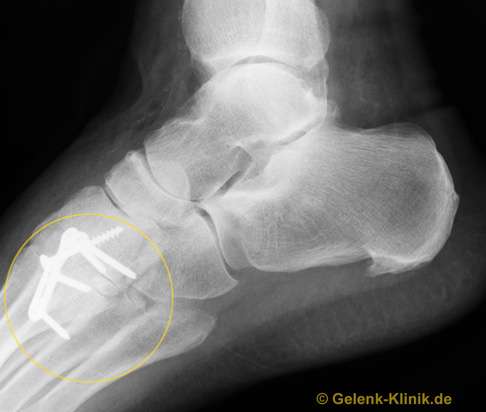

Das Röntgenbild zeigt den Zustand nach der Versteifung der Fußwurzelgelenke (gelbes Oval). Die Implantate heben die Beweglichkeit der Fußwurzelgelenke auf und ermöglichen ein stabiles Verwachsen (Arthrodese) dieser Gelenke. Die Versteifung stoppt die schmerzhaften entzündlichen Prozesse an den Gelenkflächen endgültig. Weil die Beweglichkeit der Fußwurzelknochen nicht im Vordergrund steht, ist diese Versteifung im Alltag ohne Funktionsverlust durchführbar. © Gelenk-Klinik

Das seitliche Röntgenbild zeigt den Zustand nach der Versteifung der Fußwurzelgelenke (gelbes Oval). Je nach genauer Lage und der an der Arthrose beteiligten Gelenke werden auch Platten als Implantate eingesetzt, um die Knochen stabil zu verbinden. © Gelenk-Klinik